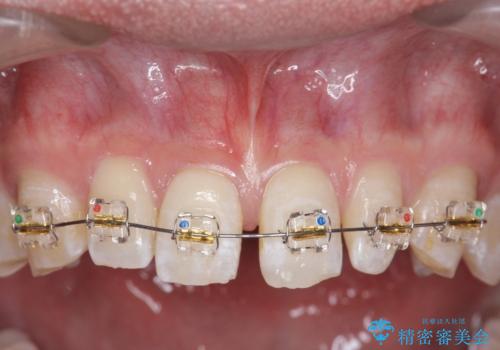

- 上顎前歯のすきっ歯が気になるといらっしゃった方の症例です。

上顎前歯のみの治療を希望されたので、部分矯正を行いました。

左上2の矮小歯はオールセラミッククラウンによる補綴を行いました。